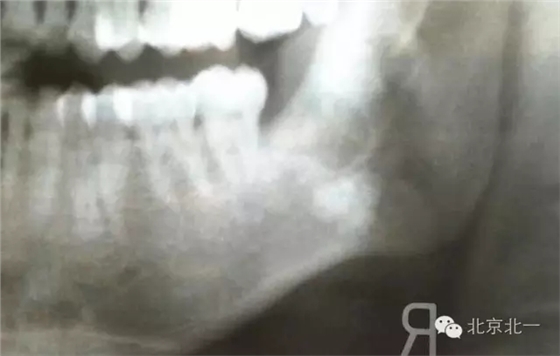

圖一:手術(shù)前(哈爾濱同行提供,接收外院患者,單位不詳)X片可見下頜骨中央高密度影像。